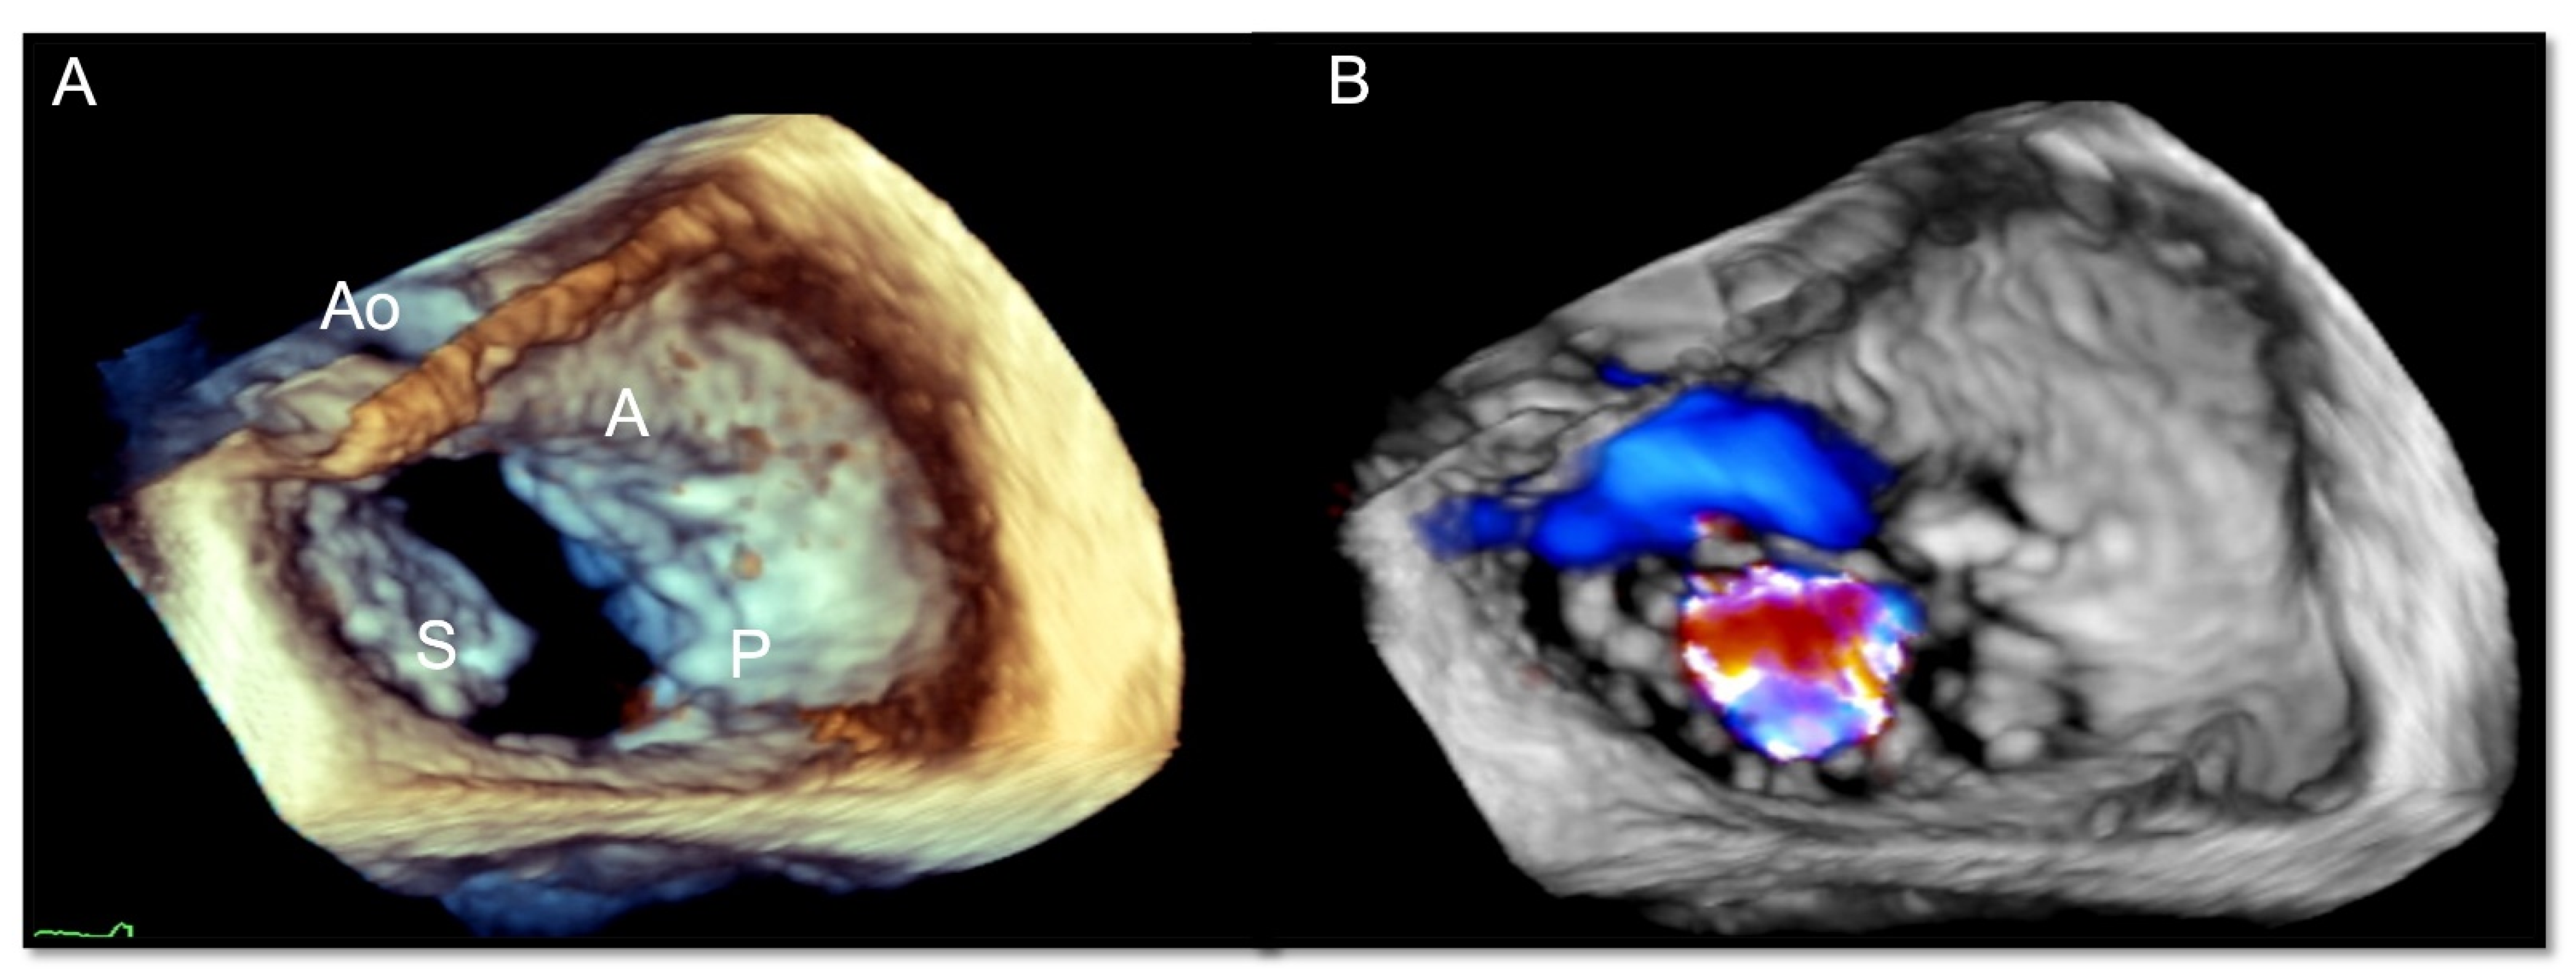

- Ancona, F.; Stella, S.; Taramasso, M.; Marini, C.; Latib, A.; Denti, P.; Grigioni, F.; Enriquez-Sarano, M.; Alfieri, O.; Colombo, A.; et al. Multimodality imaging of the tricuspid valve with implication for percutaneous repair approaches. Heart 2017, 103, 1073–1081. [Google Scholar] [CrossRef] [PubMed]

- Agricola, E.; Ancona, F.; Stella, S.; Rosa, I.; Marini, C.; Spartera, M.; Denti, P.; Margonato, A.; Hahn, R.T.; Alfieri, O.; et al. Use of Echocardiography for Guiding Percutaneous Tricuspid Valve Procedures. JACC Cardiovasc. Imaging 2017, 10, 1194–1198. [Google Scholar] [CrossRef]

- Hahn, R.T.; Nabauer, M.; Zuber, M.; Nazif, T.M.; Hausleiter, J.; Taramasso, M.; Pozzoli, A.; George, I.; Kodali, S.; Bapat, V.; et al. Intraprocedural Imaging of Transcatheter Tricuspid Valve Interventions. JACC Cardiovasc. Imaging 2019, 12, 532–553. [Google Scholar] [CrossRef]